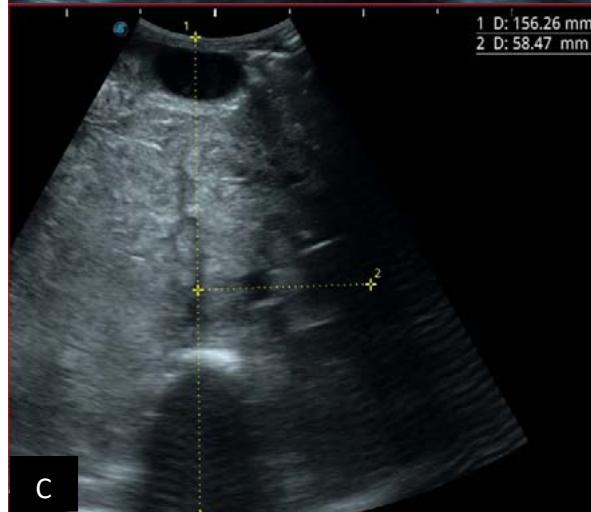

Figure 6: 9-year-old sickle cell patient, referred for abdominal bloating with significant collateral venous circulation, in whom we noted: Image A: mass, Image B: healthy renal stump, inferior polar; Image C: left transmedian extension, Image D: thrombosis of the vena cava segments: supra, retro and sub hepatic, sparing a part of the supra hepatic vena cava segment over $30~\mathrm{mm}$. Image: Ascites of great abundance, Image F: normal left kidney, Image G: splenic microcalcifications, Image H: celiac adenopathy, Image I: sub pleural pulmonary nodules with the biggest measuring $3.88 \times 3.81 \mathrm{~mm}$, Image j: left pleurisy of great abundance. Source: Dr. Frederick Tshibasu Tshienda database.